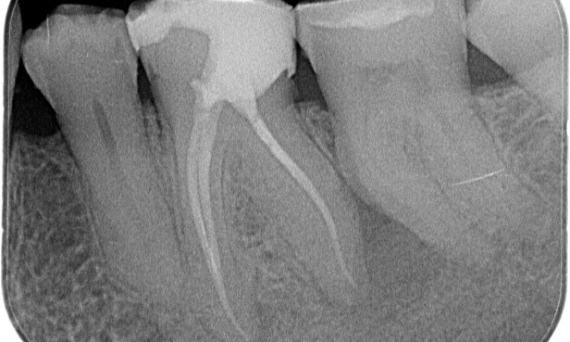

Before: Periapical radiolucency associated primarily with the distal root and loss of lamina dura on the mesial root.

After: TruNatomy was chosen in this case to allow a caries leveraged approach and a focus on pericervical dentin preservation especially on the mesial aspect where the tooth had a more minimal restoration.